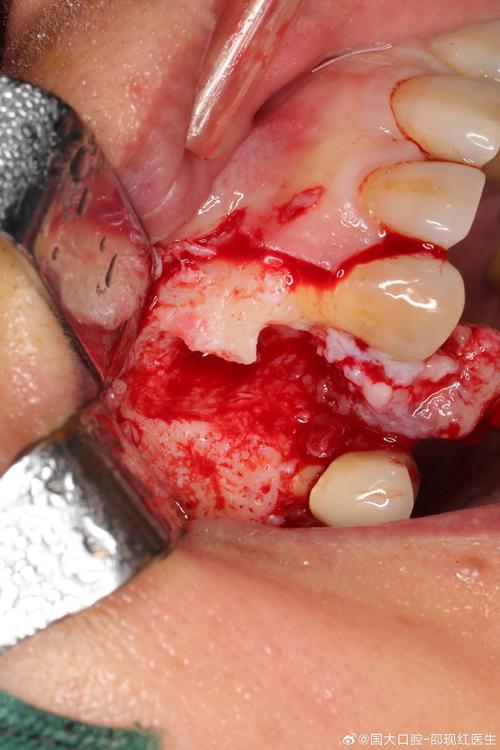

- 软组织手术:

- 牙龈切除术/成形术: 切除增生的牙龈组织,恢复健康的牙龈袖口形态。

- 翻瓣术+骨增量: 如果骨吸收较严重,需要翻开牙龈,清创,并进行骨移植。